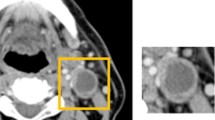

To apply a deep learning object detection technique to CT images for detecting cervical lymph nodes metastasis in patients with oral cancers, and to clarify the detection performance.

One hundred and fifty-nine metastatic and 517 non-metastatic lymph nodes on 365 CT images in 56 patients with oral squamous cell carcinoma were examined. The images were arbitrarily assigned to training, validation, and testing datasets. Using the neural network, ‘DetectNet’ for object detection, the training procedure was conducted for 1000 epochs. Testing image datasets were applied to the learning model, and the detection performance was calculated.

The learning curve indicated that the recall (sensitivity) for detecting metastatic and non-metastatic lymph nodes reached 90% and 80%, respectively, while the model performance recall by applying the test dataset was 73.0% and 52.5%, respectively. The recall for detecting level IB and Level II metastatic lymph nodes was relatively high.

A system that has the potential to automatically detect cervical lymph nodes was constructed.